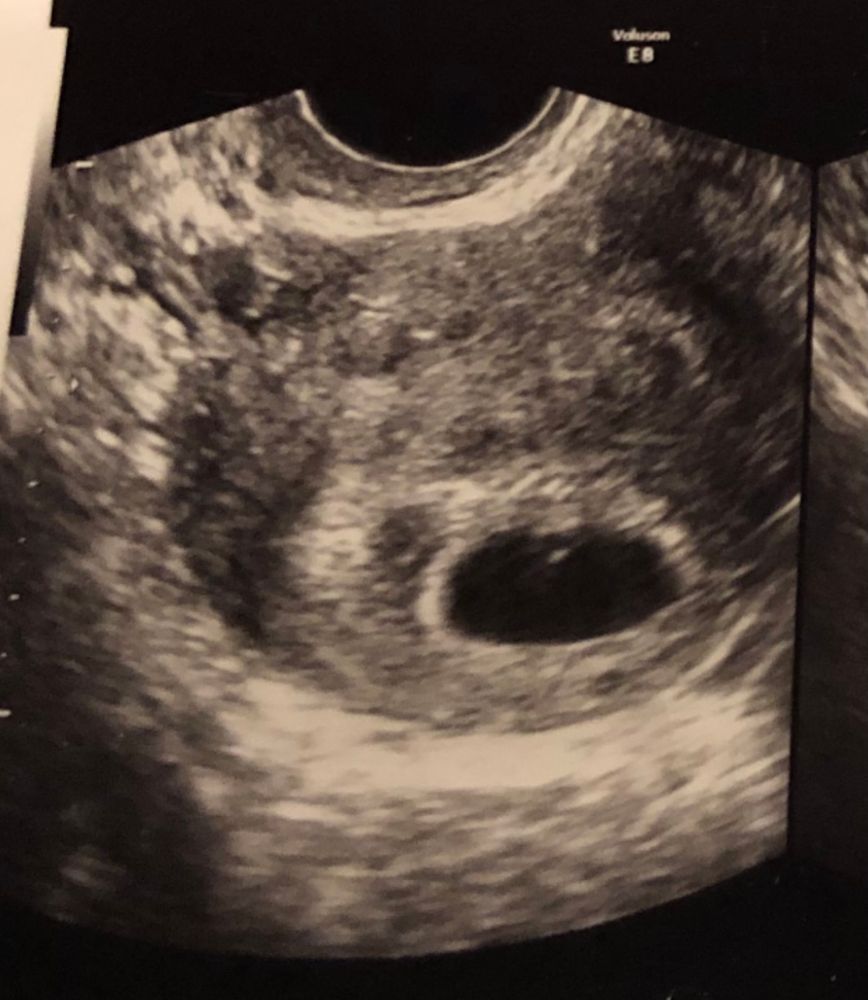

Всё у вас отлично. Верьте в малыша! У вас ещё маленький срок. У меня в 6+3 тоже не нашли эмбриона, хотя пя было 19 мм. А в 7+5 всё нашли

Алина Саидова, у вас четко виден желточный мешок. А у автора пустое пя.